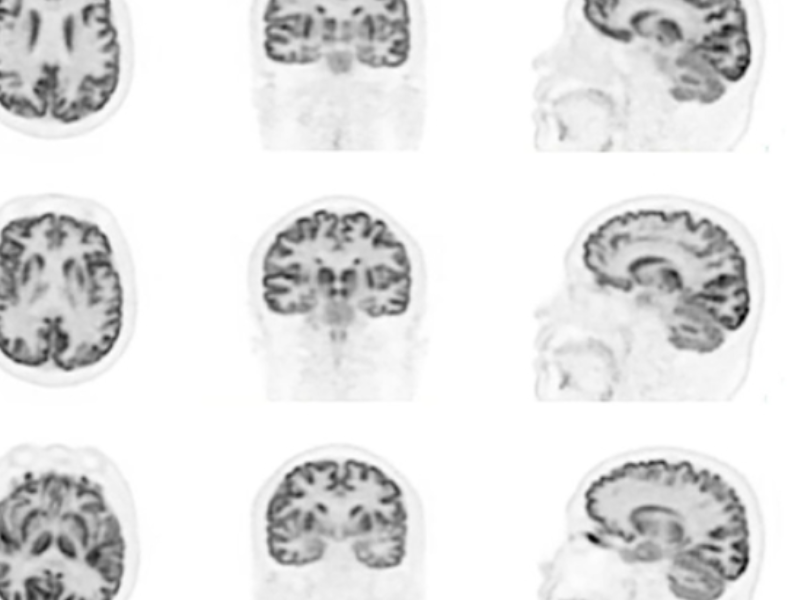

Clinical Application

Quantitative Accuracy for PET

High-Resolution PET

Lesion Detectability for PET